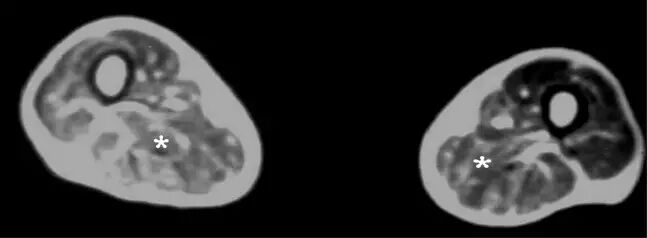

图18.中年男性线粒体肌病。 大腿的轴向T1加权MR图像显示几乎对称的脂肪浸润和四头肌肌肉(星号)的萎缩。

![]()